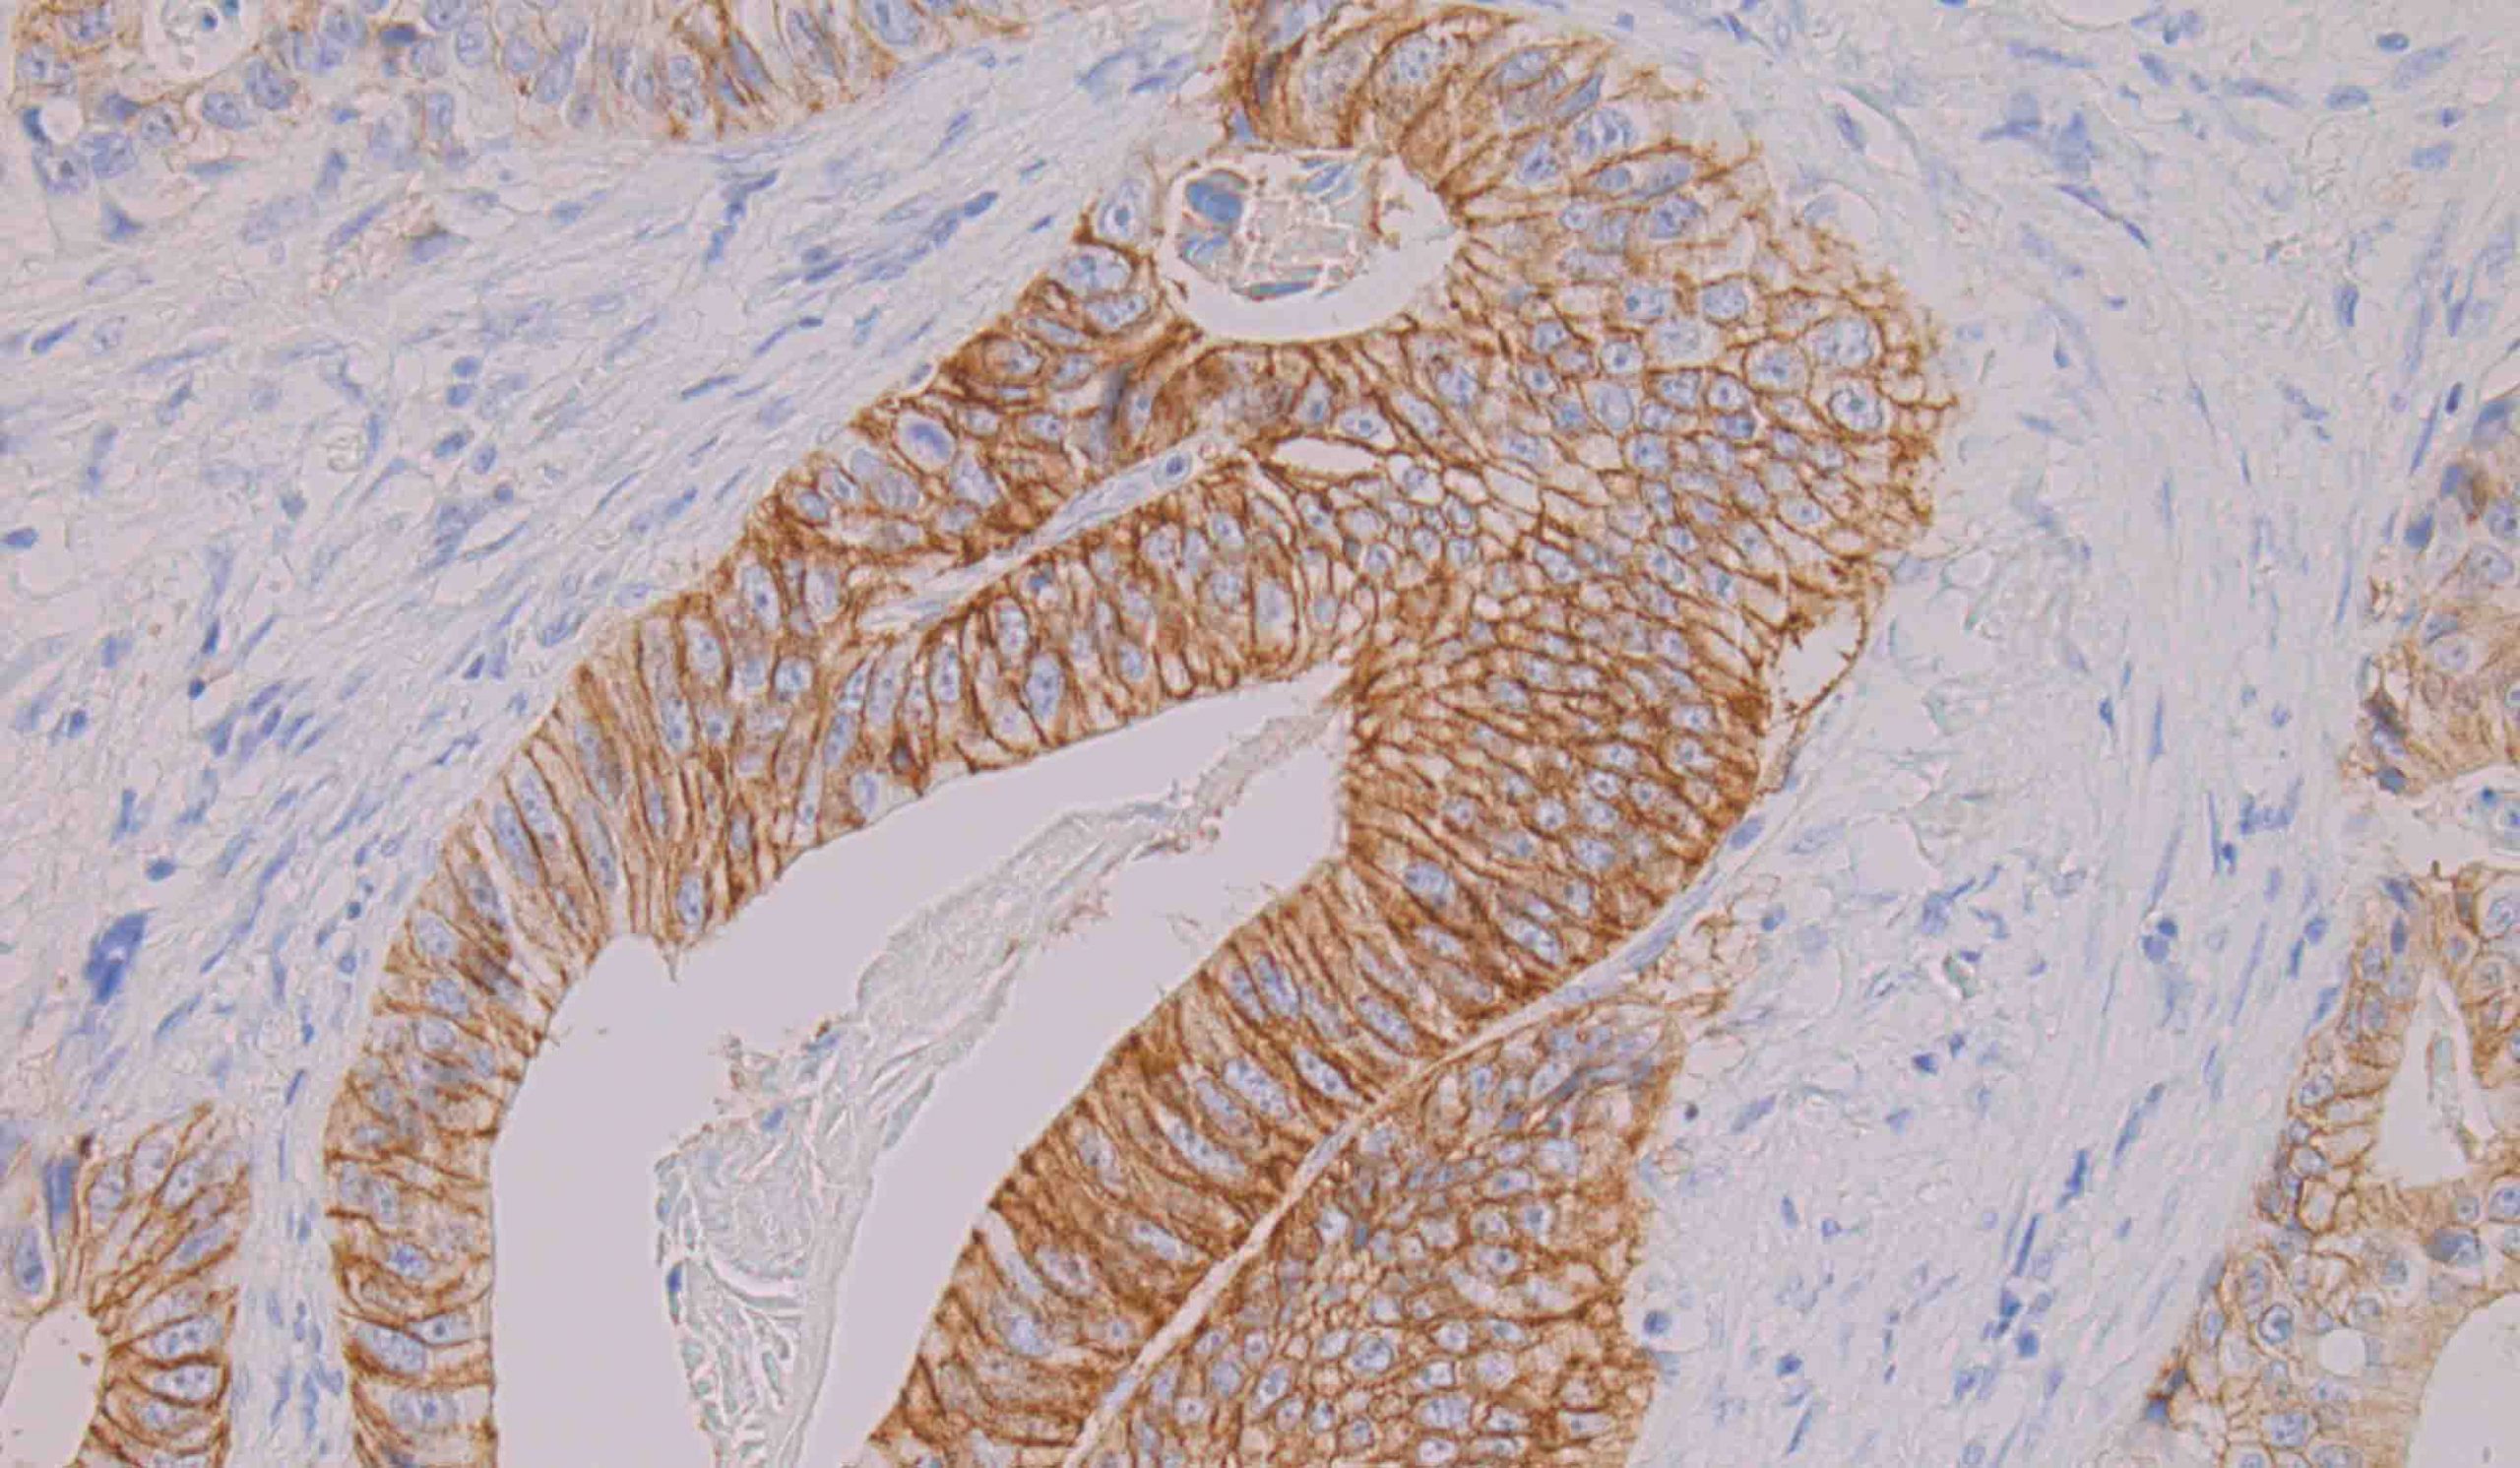

Inmunohistoquímica

La tinción inmunohistoquímica permite la detección de constituyentes tisulares o celulares (antígenos) mediante interacciones antígeno-anticuerpo, identificando el sitio de unión específica del anticuerpo bien por marcaje directo del anticuerpo (método directo) bien con el uso de un método de marcaje secundario (método indirecto).

Mediante el equipo de inmunotinción automática del que disponemos en la Unidad, se consigue automatizar y estandarizar la técnica de tinción inmunohistoquímica, reduciendo el tiempo de realización. Contamos con un servicio de optimización o puesta a punto de anticuerpos (tinciones inmunohistoquímicas) y la asesoría en la búsqueda de anticuerpos adecuados para la aplicación de la técnica inmunohistoquímica en diferentes condiciones con el fin de obtener resultados homogéneos y reproducibles.